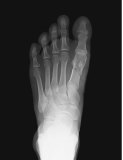

Metatarsal fracture

age 16

Femur fracture

age 13

Tibial fracture

age 57